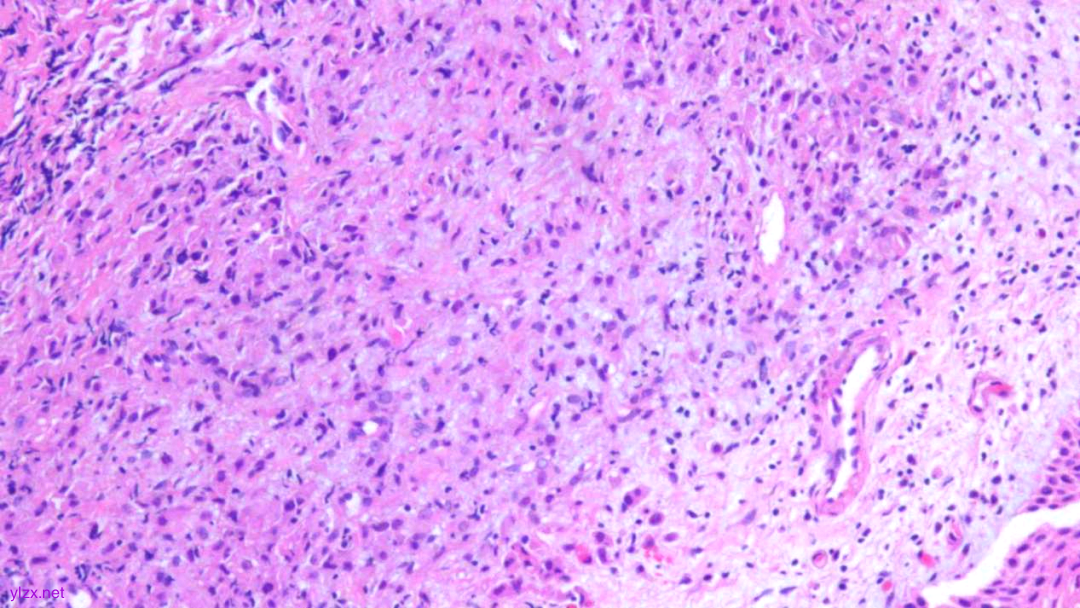

HE:

黏膜间质内见胞浆丰富,红染及粉染瘤细胞弥漫分布,部分细胞核稍偏位,核圆形,稍增大,深染,见核仁,穿插在固有腺之间,伴少量炎细胞浸润。

瘤组织穿插在固有腺之间,较弥漫,核稍增大,深染

瘤细胞稀疏排列,胞浆粉染及红染,宽阔

瘤细胞核圆形,见核仁,部分细胞核偏位,未见核分裂象

瘤细胞核仁明显